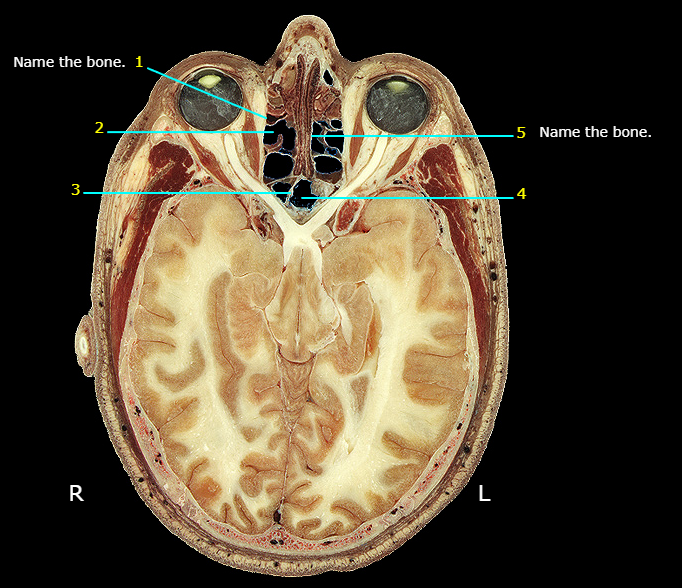

Name the structure

Anterior nasal aperture

Lacrimal

Name #4

Nasal

Name #2

Nasal cavity

Nasal septum